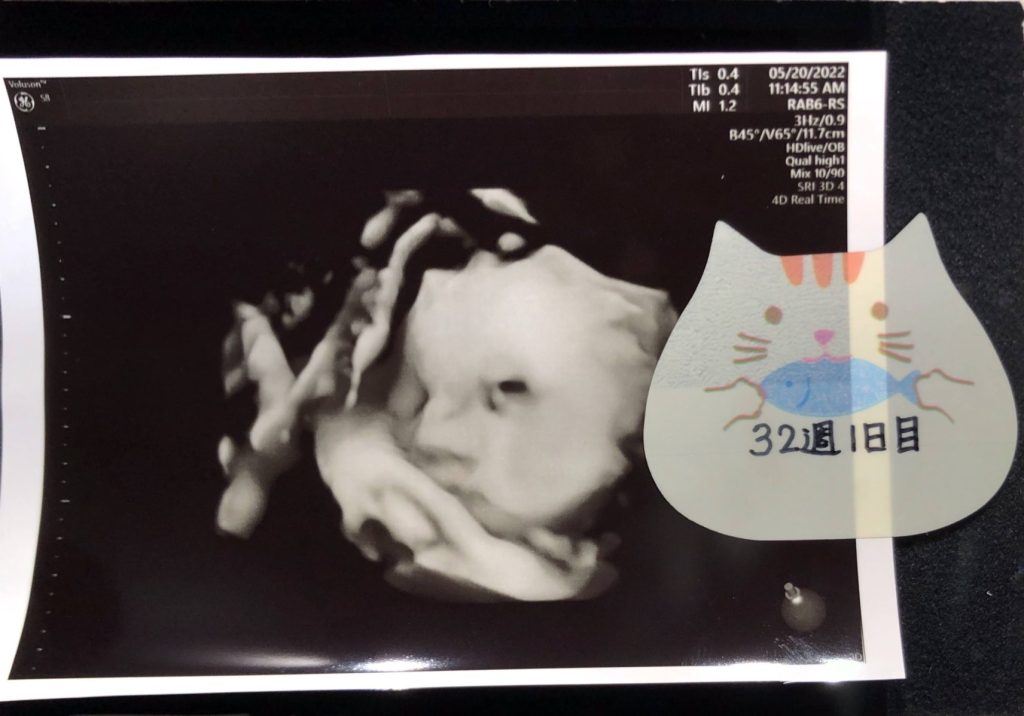

前回はエコー写真をデジタルにされていた方もいましたよ!